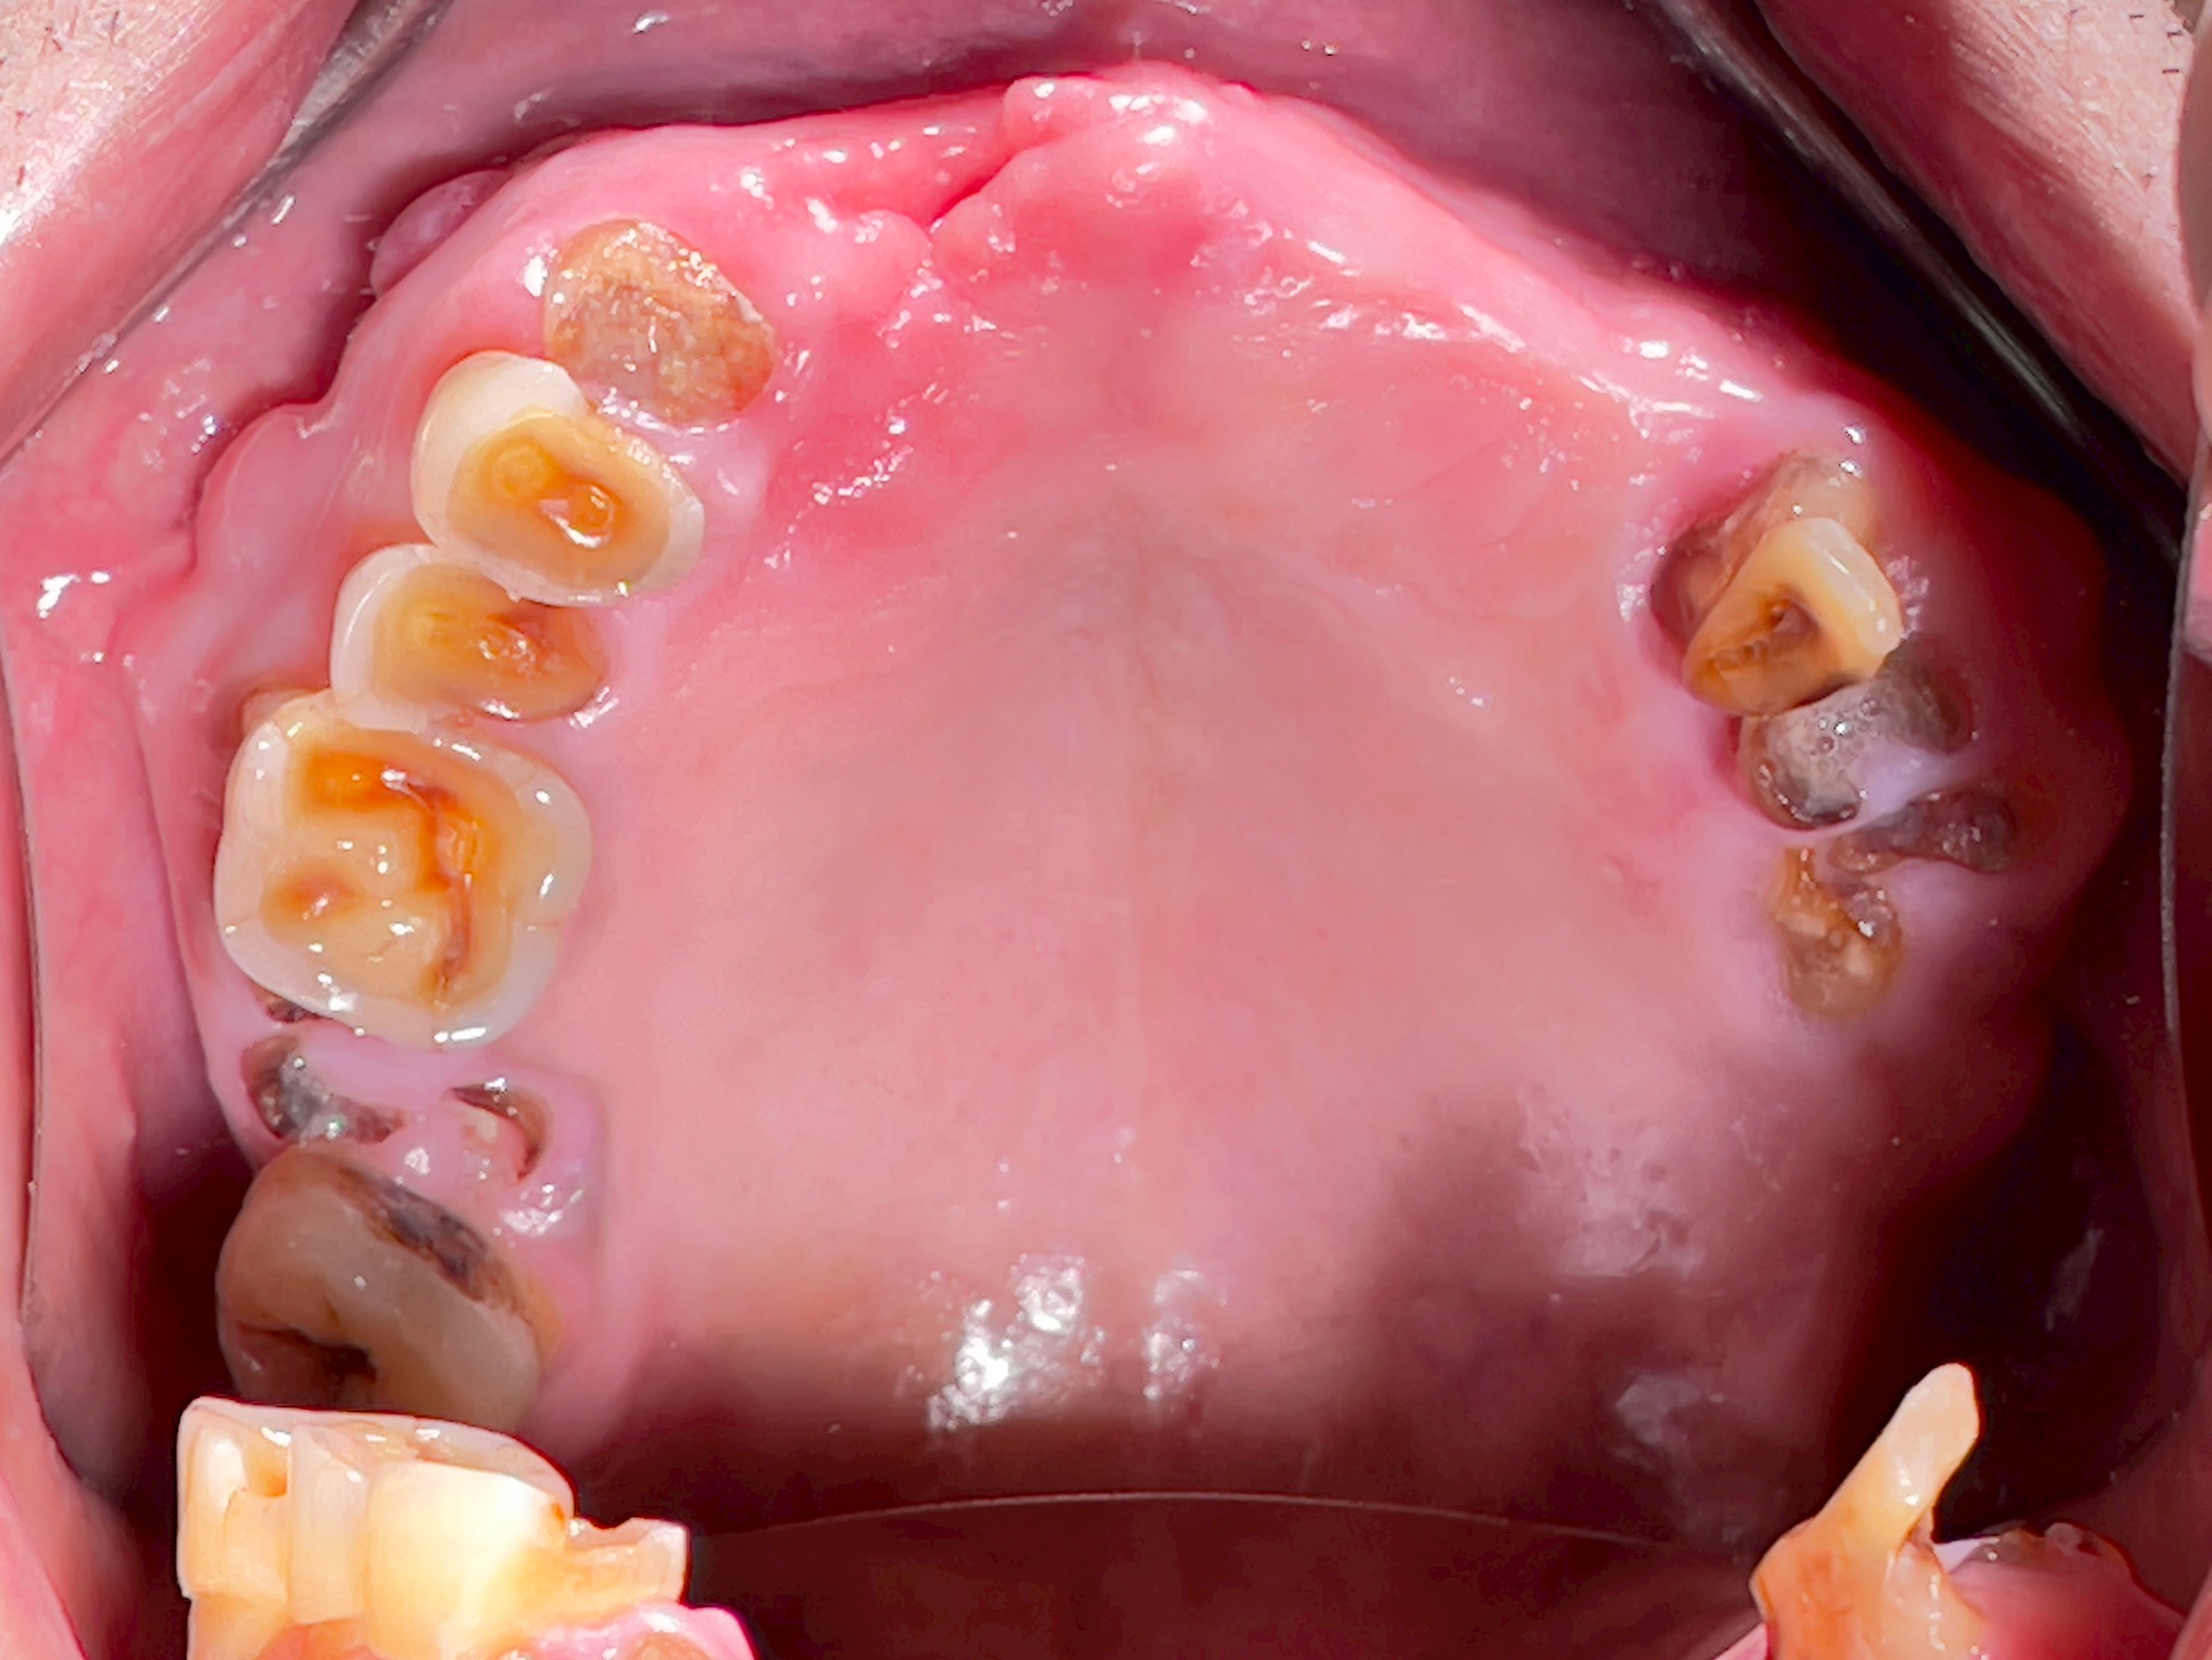

All-on-4 Implants Lower Jaw + Partial Denture Upper Jaw